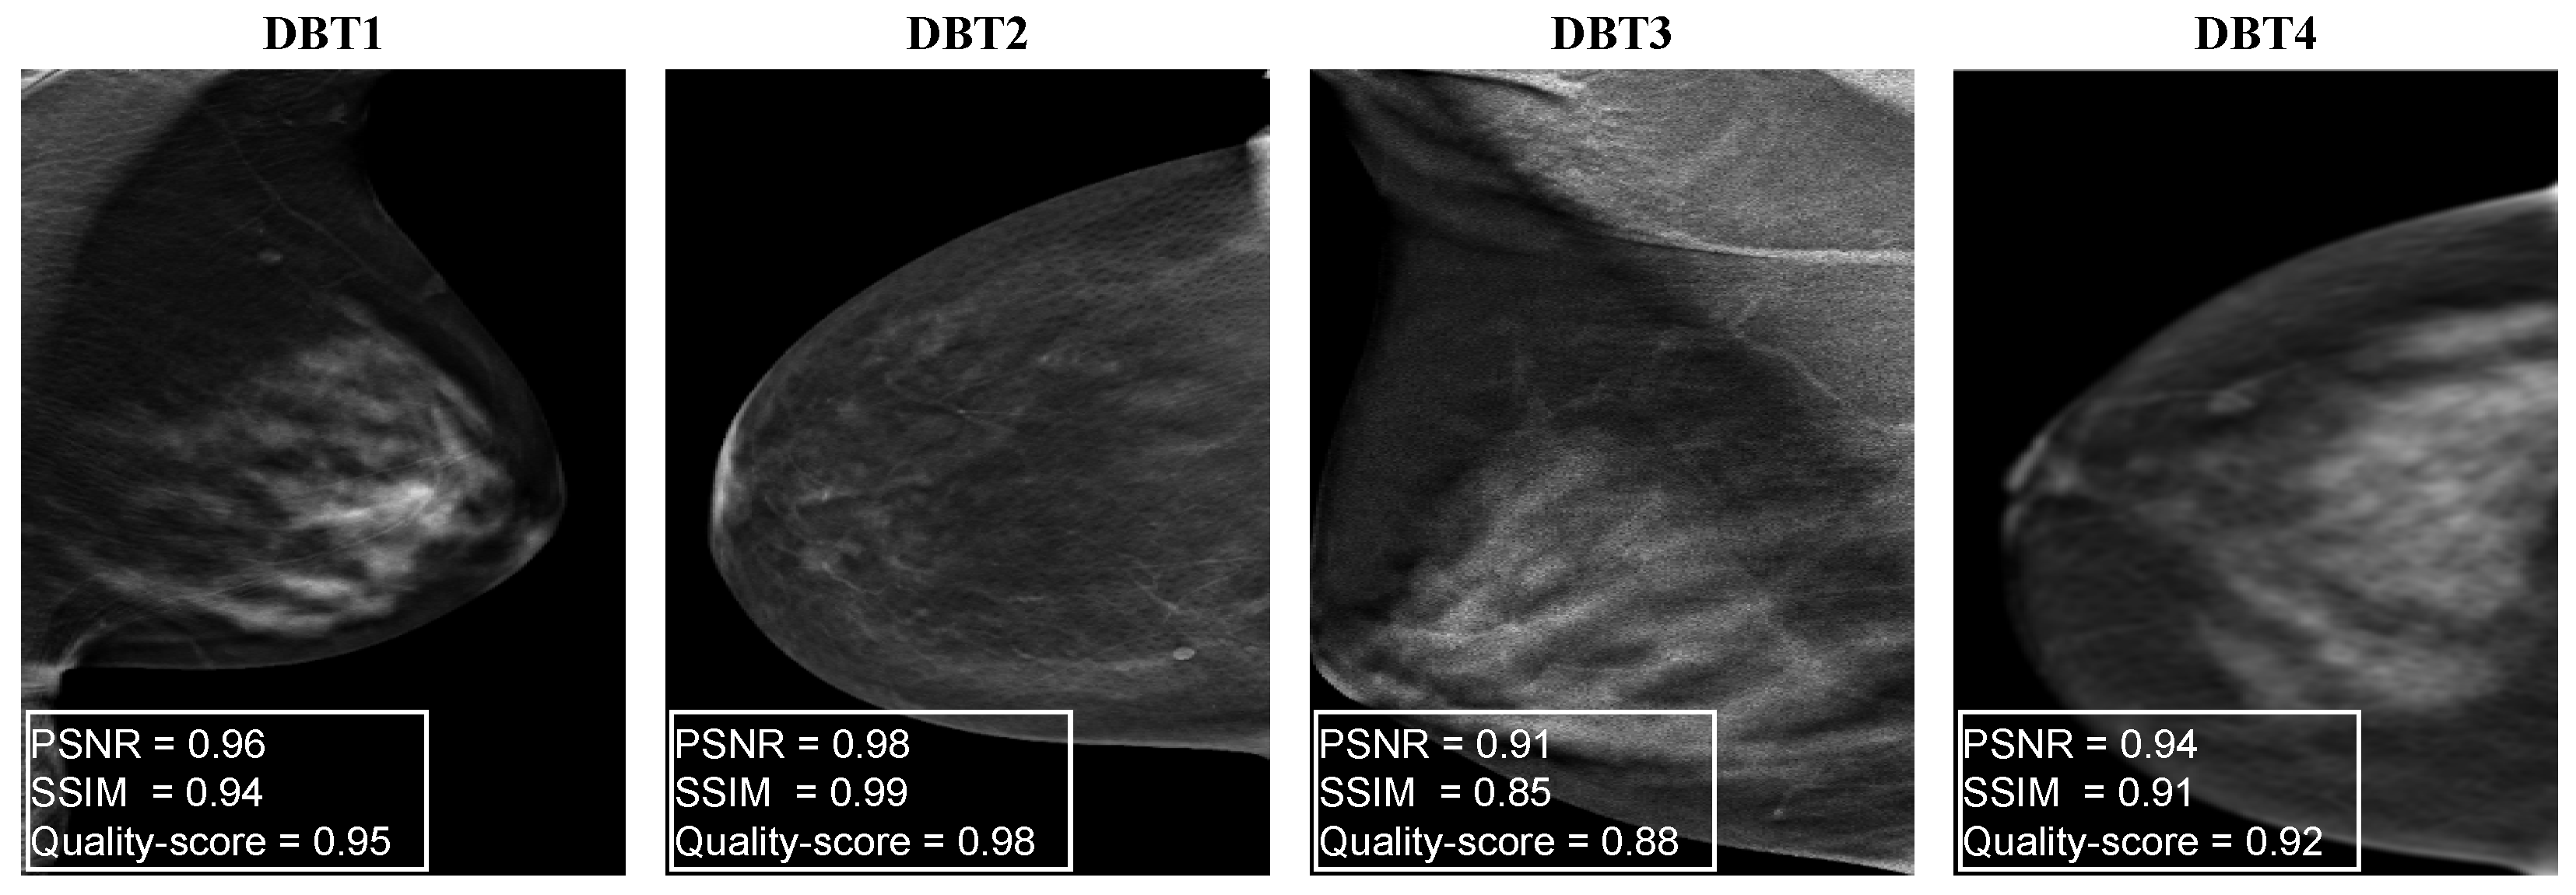

Appendix A.2. Performance Evaluation of the Proposed DBT NR-IQA Method